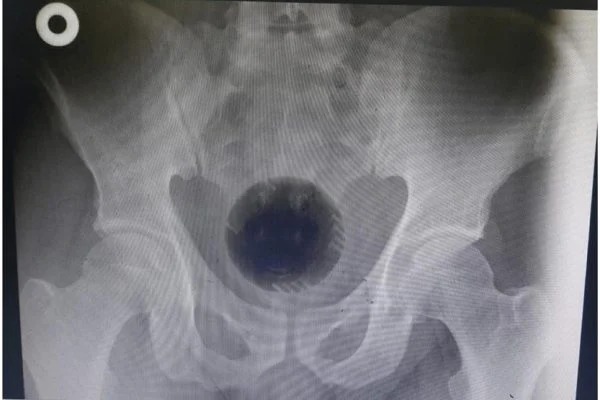

Homem passa por cirurgia para tirar bola de sinuca do ânus

Um homem de 51 anos precisou passar por uma cirurgia para retirar uma bola do ânus. O caso aconteceu em Irbid, uma cidade da Jordânia.

Segundo informações do “Daily Mail”, o homem chegou acanhado e com vergonha no hospital alegando que havia tentado uma nova forma de tratar suas hemorróidas. Ele chegou à instituição acompanhado de sua mulher.

O caso foi relatado no International Journal of Surgery Case Reports. Médicos responsáveis pela extração disseram que o paciente havia tentado tirar a bola de dentro de seu corpo utilizando uma colher e também uma chave de fenda.

Quando chegou ao Hospital Universitário Princesa Basma, os médicos tentaram retirar o objeto manualmente, mas não obtiveram sucesso. Assim, ele passou a noite no hospital em observação. Por fim, foi realizada uma  cirurgia de retirada pelo estômago. (Com informações pelo “Daily Mail”).